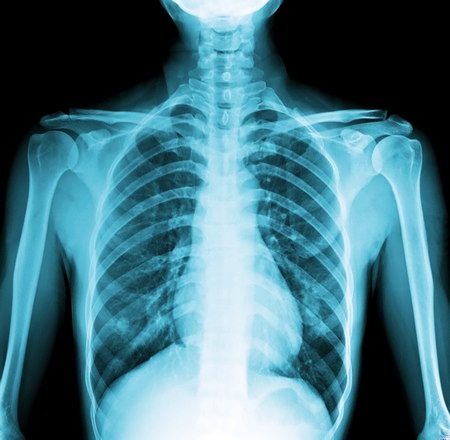

Именно такие водородные колебания позволяют построить картинку, из которой видно состояние внутренних органов и систем. Радиация тут полностью отсутствует. В этом состоит кардинальное отличие МРТ от рентгена. Именно радиация оказывает негативное влияние на органы человека, и в больших дозах она крайне опасна.

МРТ и рентген – что безопаснее

Эти аппаратные способы диагностики относятся к самым популярным. Следует отметить, что:

- При рентгене на пациента воздействует поток ионов. У него слабая мощность, потому один сеанс рентгена не может нанести какой-либо вред. Доза излучения слишком мала.

- Специфика рентгена состоит в том, что полученные дозы излучения плюсуются. Его нельзя применять многократно за короткий промежуток времени. Дозы накапливаются, и при повторном обследовании негативный эффект усиливается. Крайне нежелательно за короткий промежуток времени повторять рентген несколько раз. Негативное воздействие от предыдущей дозы просто не успеет исчерпаться. Со временем ткани восстанавливаются, а если повторять ионизирующее воздействие часто, клетки и ткани могут повреждаться.

- Рентген противопоказан при некоторых патологиях и беременности. Радиация может стать губительной для плода.

- Нежелателен рентген и при грудном вскармливании. Кормящая мать должна обследоваться другими методами.

Некоторые пациенты отождествляют магнитно-резонансный метод и рентген. Это неправильно. Оба метода, хоть и аппаратные, но в их основе лежат совершенно разные физические процессы. При МРТ здоровью не угрожает вредное воздействие даже при повторной процедуре, и у неё абсолютно отсутствует ионизирующее излучение.